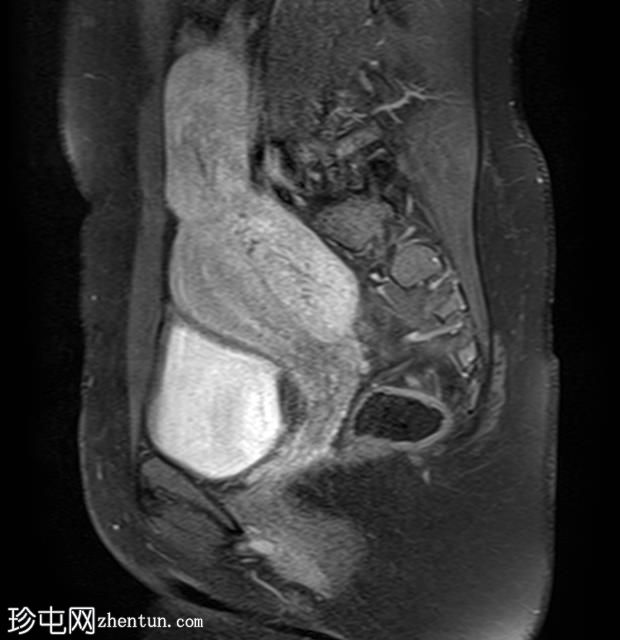

矢状位

T2加权像

其中一个位于子宫上方,T2加权像呈中等信号,中心区域呈高信号,增强T1脂肪抑制像未见强化。右侧卵巢增大,增厚的血管蒂扭曲,未见强化,轴位和矢状位T2加权像均显示清晰。